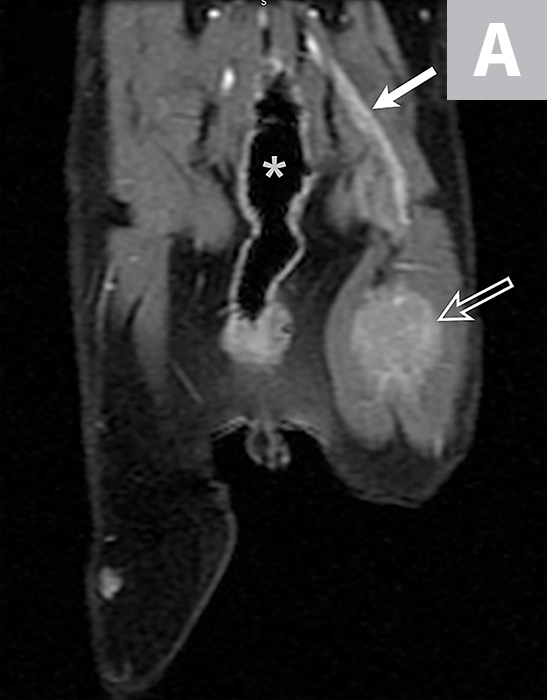

From radiologykey.com

Thymic Epithelial Neoplasms Radiology Key Thymic Neoplasm Feline Thymic tumors are abnormal growths of tissues of the thymus gland, and are rare in cats. Its cause is unknown, and diagnosis. A thymoma is a tumor originating from the epithelium of the thymus (the layer of tissue covering the thymus). In this report, we present the full diagnostic characteristics of a young cat with a cranial mediastinal mass diagnosed. Thymic Neoplasm Feline.

Thymic Epithelial Neoplasms Radiology Key Thymic Neoplasm Feline In this report, we present the full diagnostic characteristics of a young cat with a cranial mediastinal mass diagnosed as a cystic type. Its cause is unknown, and diagnosis. Thymic tumors are abnormal growths of tissues of the thymus gland, and are rare in cats. Thymoma is a rare neoplasm seen in aged cats that derives from thymic epithelial cells. Thymic Neoplasm Feline.